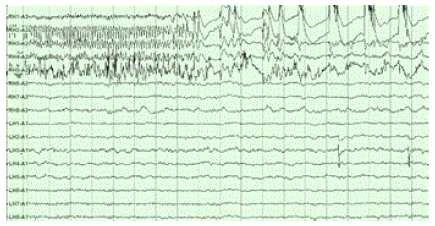

해마는 두 가지 주요한 활동 "모드"를 보인다. 각 모드는 신경 개체군 활동과 뇌파도 (EEG)로 측정된 전기 활동의 뚜렷한 패턴과 관련이 있다. 이러한 모드는 관련 EEG 패턴에 따라 세타파와 큰 불규칙 활동 (LIA)으로 명명되었다. 아래 설명은 가장 광범위하게 연구된 동물인 쥐에 대한 것이다.[93]

세타 모드는 활동적이고 경계적인 행동 상태(특히 이동)와 REM (꿈 수면) 중에 나타난다.[86] 세타 모드에서 EEG는 6~9 Hz의 주파수 범위를 갖는 크고 규칙적인 파동이 지배적이며, 해마 뉴런의 주요 그룹(피라미드 세포와 과립 세포)은 희소한 개체군 활동을 보인다.

LIA 모드는 서파 수면 (비꿈 수면)과 휴식 또는 식사와 같은 각성 부동 상태에서 나타난다.[86] LIA 모드에서 EEG는 25–50밀리초 동안 지속되는, 무작위적 시간대의 큰 편향인 날카로운 파동이 지배적이다. 날카로운 파동은 종종 세트로 생성되며, 세트는 최대 5개 이상의 개별 날카로운 파동을 포함하고 최대 500ms 동안 지속된다. 해마 내 뉴런의 스파이킹 활동은 날카로운 파동 활동과 매우 상관관계가 있다.

이러한 두 가지 해마 활동 모드는 쥐뿐만 아니라 영장류에서도 볼 수 있다. 다만, 영장류 해마에서 강력한 세타 리듬을 관찰하기 어렵다는 점을 제외하고는, 질적으로 유사한 날카로운 파동과 유사한 상태 의존적인 신경 개체군 활동 변화가 있다.[87]

6. 1. 세타파 (Theta Rhythm)

세타파를 생성하는 주된 전류는 주로 내후피질, CA3 및 피라미드 세포의 수상돌기(가지돌기)의 밀집된 신경층에서 만들어진다. 세타파는 뇌파도(EEG)에서 볼 수 있는 가장 큰 신호 중 하나이며, ''해마 세타 리듬''이라고도 한다.[88] 어떤 상황에서는 뇌파가 3~10 Hz의 규칙적인 파동에 의해 지배되는데, 이는 종종 수 초 동안 지속된다. 이러한 파동은 역치하 막 전위를 나타내며, 해마 뉴런의 발화를 강력하게 조절하고, 이동 파동 패턴으로 해마 전체에서 동기화된다.[89] 삼연접 회로는 해마 내의 신경전달 중계 역할을 하며, 많은 뇌 영역과 상호 작용한다. 설치류를 대상으로 한 실험에서는 삼연접 회로가 해마 세타 리듬을 생성한다는 결과가 나왔다.[90]

세타 리듬은 토끼와 설치류에서 매우 뚜렷하게 나타나며, 고양이와 개에서도 명확하게 관찰된다. 영장류에서 세타파가 관찰되는지는 아직 확실하지 않다.[91] 실험쥐 (가장 많이 연구된 동물)에서 세타파는 주로 두 가지 조건에서 관찰된다. 첫째, 동물이 걷거나 다른 방식으로 주변 환경과 적극적으로 상호 작용할 때, 둘째, 렘수면 동안이다.[92] 세타파의 기능은 아직 명확하게 밝혀지지 않았지만, 여러 가지 이론이 제시되었다.[93] 가장 널리 알려진 가설은 학습과 기억에 관련시키는 것이다. 예를 들어, 세타 리듬의 위상이 뉴런 자극 시간에 해당 뉴런의 시냅스에 미치는 영향을 형성하는 방식이 있다. 이는 세타 리듬이 시냅스 가소성에 의존하는 학습과 기억에 영향을 줄 수 있다는 것을 의미한다.[94] 내측 중격의 손상이 심각한 기억 장애를 일으킨다는 것은 잘 알려져 있다.[95] 그러나 내측 중격은 세타의 조절기일 뿐만 아니라, 해마로의 콜린성 신호 전달의 주요 원천이기도 하다.[17] 중격 손상이 세타 리듬을 제거함으로써 특정 효과를 나타내는지는 아직 밝혀지지 않았다.[96]

6. 2. 예파-잔물결 복합체 (Sharp Wave-Ripple Complex)

동물이 주변 환경과 상호작용하지 않는 수면 또는 휴식 시간 동안 해마 뇌파 (EEG)는 세타파보다 진폭이 약간 더 큰 불규칙적인 느린 파동 패턴을 보인다. 이 패턴은 때때로 '예파'라고 불리는 큰 급증으로 인해 중단된다.[97] 이러한 현상은 CA3 및 CA1의 피라미드 세포에서 50~100밀리초 동안 지속되는 스파이크 활동의 폭발과 관련이 있다. 또한 쥐의 경우 150~200 Hz 범위의 주파수를 갖는 "리플"이라고 불리는 단기 고주파 뇌파 진동과도 관련이 있으며, 이들을 통틀어 예파와 리플이라고 한다. 예파는 수면 중에 가장 빈번하게 발생하며(쥐의 경우 평균적으로 초당 약 1회), 시간적 패턴은 매우 불규칙하다. 비활성 각성 상태에서는 예파가 덜 빈번하게 발생하며 일반적으로 더 작다. 예파는 인간과 원숭이에서도 관찰되었다. 마카크 원숭이의 경우 예파가 강력하게 나타나지만 쥐만큼 자주 발생하지는 않는다.[87]예파의 가장 흥미로운 측면 중 하나는 기억과 관련이 있다는 것이다. Wilson과 McNaughton(1994),[98] 및 수많은 후속 연구에 따르면 해마 위치 세포가 겹치는 공간 발화 필드를 가지고 있어(따라서 종종 거의 동시에 발화함) 행동 세션 이후 수면 중에 상관된 활동을 보이는 경향이 있다고 보고했다. 일반적으로 '재활성화'라고 알려진 이 상관 관계의 증가는 주로 예파 동안 발생하는 것으로 밝혀졌다.[99] 예파는 실제로 행동 중에 기억된 신경 활동 패턴의 재활성화이며, 해마 내 시냅스 연결의 강화에 의해 유발된다는 것이 제안되었다.[100] 이 아이디어는 Buzsáki 등이 주장하는 "2단계 기억" 이론[101]의 핵심 구성 요소를 형성하며, 이 이론은 기억이 행동 중에 해마 내에 저장된 다음 나중에 수면 중에 신피질로 전송된다고 제안한다. 헤브 이론에서 예파는 해마 출력 경로의 피질 목표에서 시냅스 변화를 유도하기 위해 제안된 시냅스 전 세포에 의한 시냅스 후 세포의 지속적인 반복 자극으로 간주된다.[102] 수면 중 또는 부동 시 예파와 리플의 억제는 행동 수준에서 표현되는 기억을 방해할 수 있지만,[103][104] 그럼에도 불구하고 새롭게 형성된 CA1 위치 세포 코드는 공간적 요구가 없는 작업에서 예파와 리플이 사라진 수면 후에도 다시 나타날 수 있다.[105]